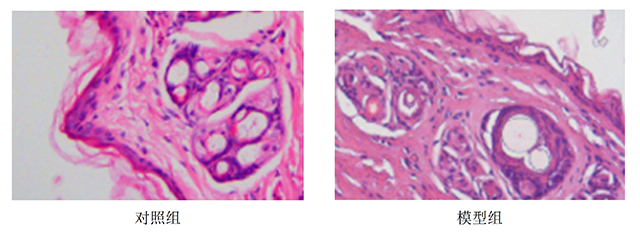

评价指标:ELISA检测、HE染色

皮肤组织HE染色